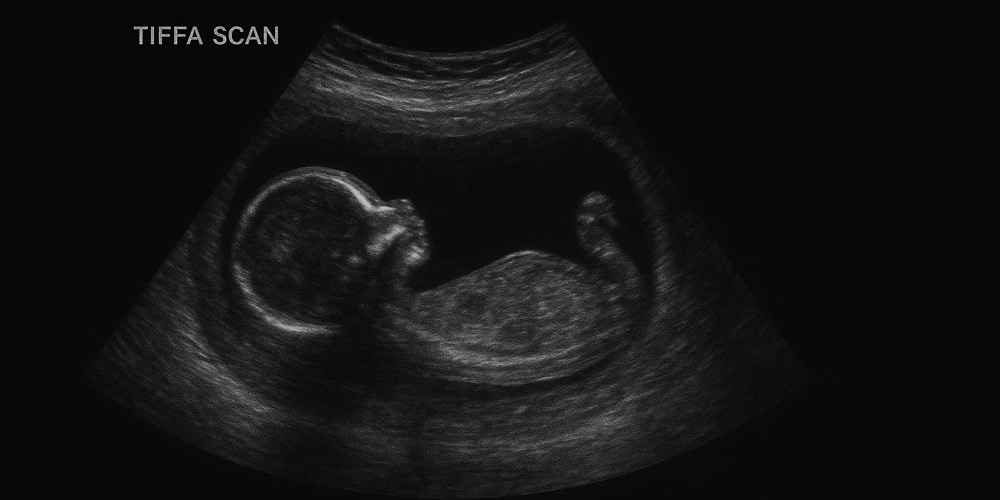

A TIFFA scan (Targeted Imaging for Fetal Anomalies) is a detailed ultrasound test which was done during pregnancy to check how your baby is growing and developing inside the mother’s stomach. It helps doctors see if all your baby’s organs through an ultrasound technique like the heart, brain, spine, kidneys, and limbs are forming normally or abnormally.

TIFFA Ultrasound is done with high-definition imaging technologies, where the sonographer uses some special gel on the abdomen of the mother and moves a transducer very smoothly over the abdomen to get clearer images of the baby inside the womb. Dr. Aravind's IVF gives that comfort level through the whole process and fully briefs mothers concerning what happens during every step.

She will be lying comfortably on an examination bed, and the sonographer will carry out a detailed photography of the fetus using ultrasound when she comes for a TIFFA scan. This is a completely safe and non-invasive procedure. Dr. Aravind's IVF ensures that their staff makes every mother really relaxed and well-informed when they are under scan and before coming for a scan.

The doctor descends deep below the analysis of the brain, heart, kidneys, and limbs of the child to ensure that all images are representative of normal development. Well-versed and professionally trained, the radiology team at Dr. Aravind's IVF creates report formats that are valid and well-evidenced, thereby allowing obstetricians to plan further care steps if necessary.